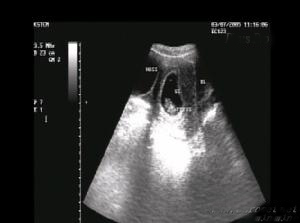

(一)B超:一般為單側或雙側卵巢囊性增大,表面光滑,邊界清楚,直徑小於5cm。

在B超的表現為雙側或單側卵巢囊性增大、囊壁光滑、囊內反射呈均勻無回聲區,或有分隔或小網狀結構。孕早期發現可於孕中期消失,亦可發現後一直保持有大小,經B超監測後一般可明確良性診斷。臨床也有極少數孕期增大,出現腹水,囊內液為淡血性的嚴重卵巢黃素瘤報導。